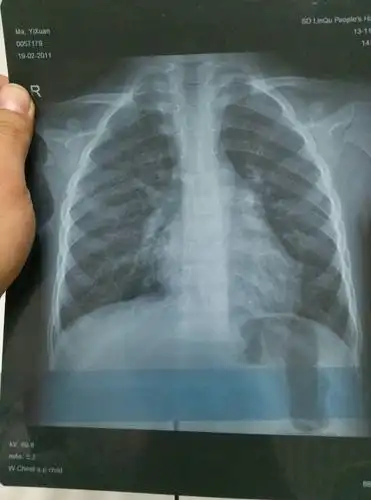

大家来看看这张小孩子 的胸片

小孩两个月了,不发烧,偶尔咳两下,拍片子诊断为支气管肺炎,医请各位